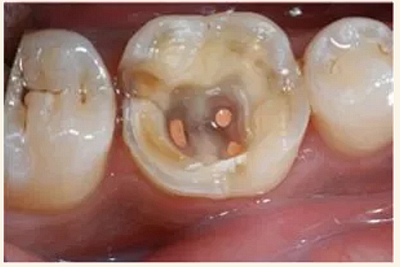

根管治療術(shù)又稱牙髓治療,是牙醫(yī)學(xué)中治療牙髓壞死和牙根感染的一種手術(shù)。該手術(shù)保留了牙齒,先是揭開髓室,頂敞開通路,用拔髓針拔除感染的牙髓。在用擴挫針擴凈根管壁,之后在根管內(nèi)封消炎藥,最后再用牙膠尖充填,手術(shù)繁瑣,一般要2-4次就診才能完成。隨著技術(shù)和材料的進步,活髓牙一次性根管治療術(shù),也在臨床應(yīng)用。

1.開髓:即將患牙打開,暴露髓腔。

2.根管預(yù)備:通過不同器械在牙根里面切削清理擴大根管。